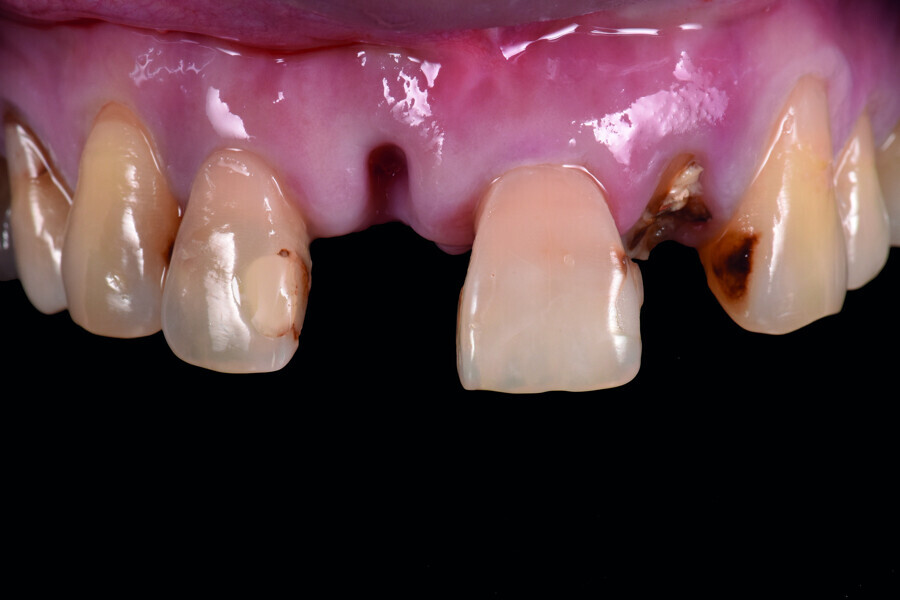

Fig. 1: Pre-op frontal view of the anterior teeth.